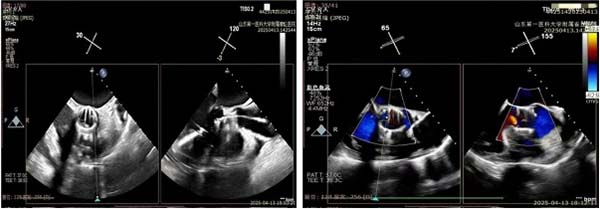

随后,团队迅速转换至TAVR程序。王安彪与朱梅配合,将瓣膜装载并引导至主动脉根部,通过TEE确认瓣环定位无误后,平稳释放瓣膜。超声即时显示人工瓣架固定牢靠,瓣叶开启顺畅,瓣周无间隙回声;多普勒测得瓣区最高流速225 cm/s,圧差20 mmHg,提示置换效果优异。

主动脉瓣植入,主动脉瓣返流明显改善